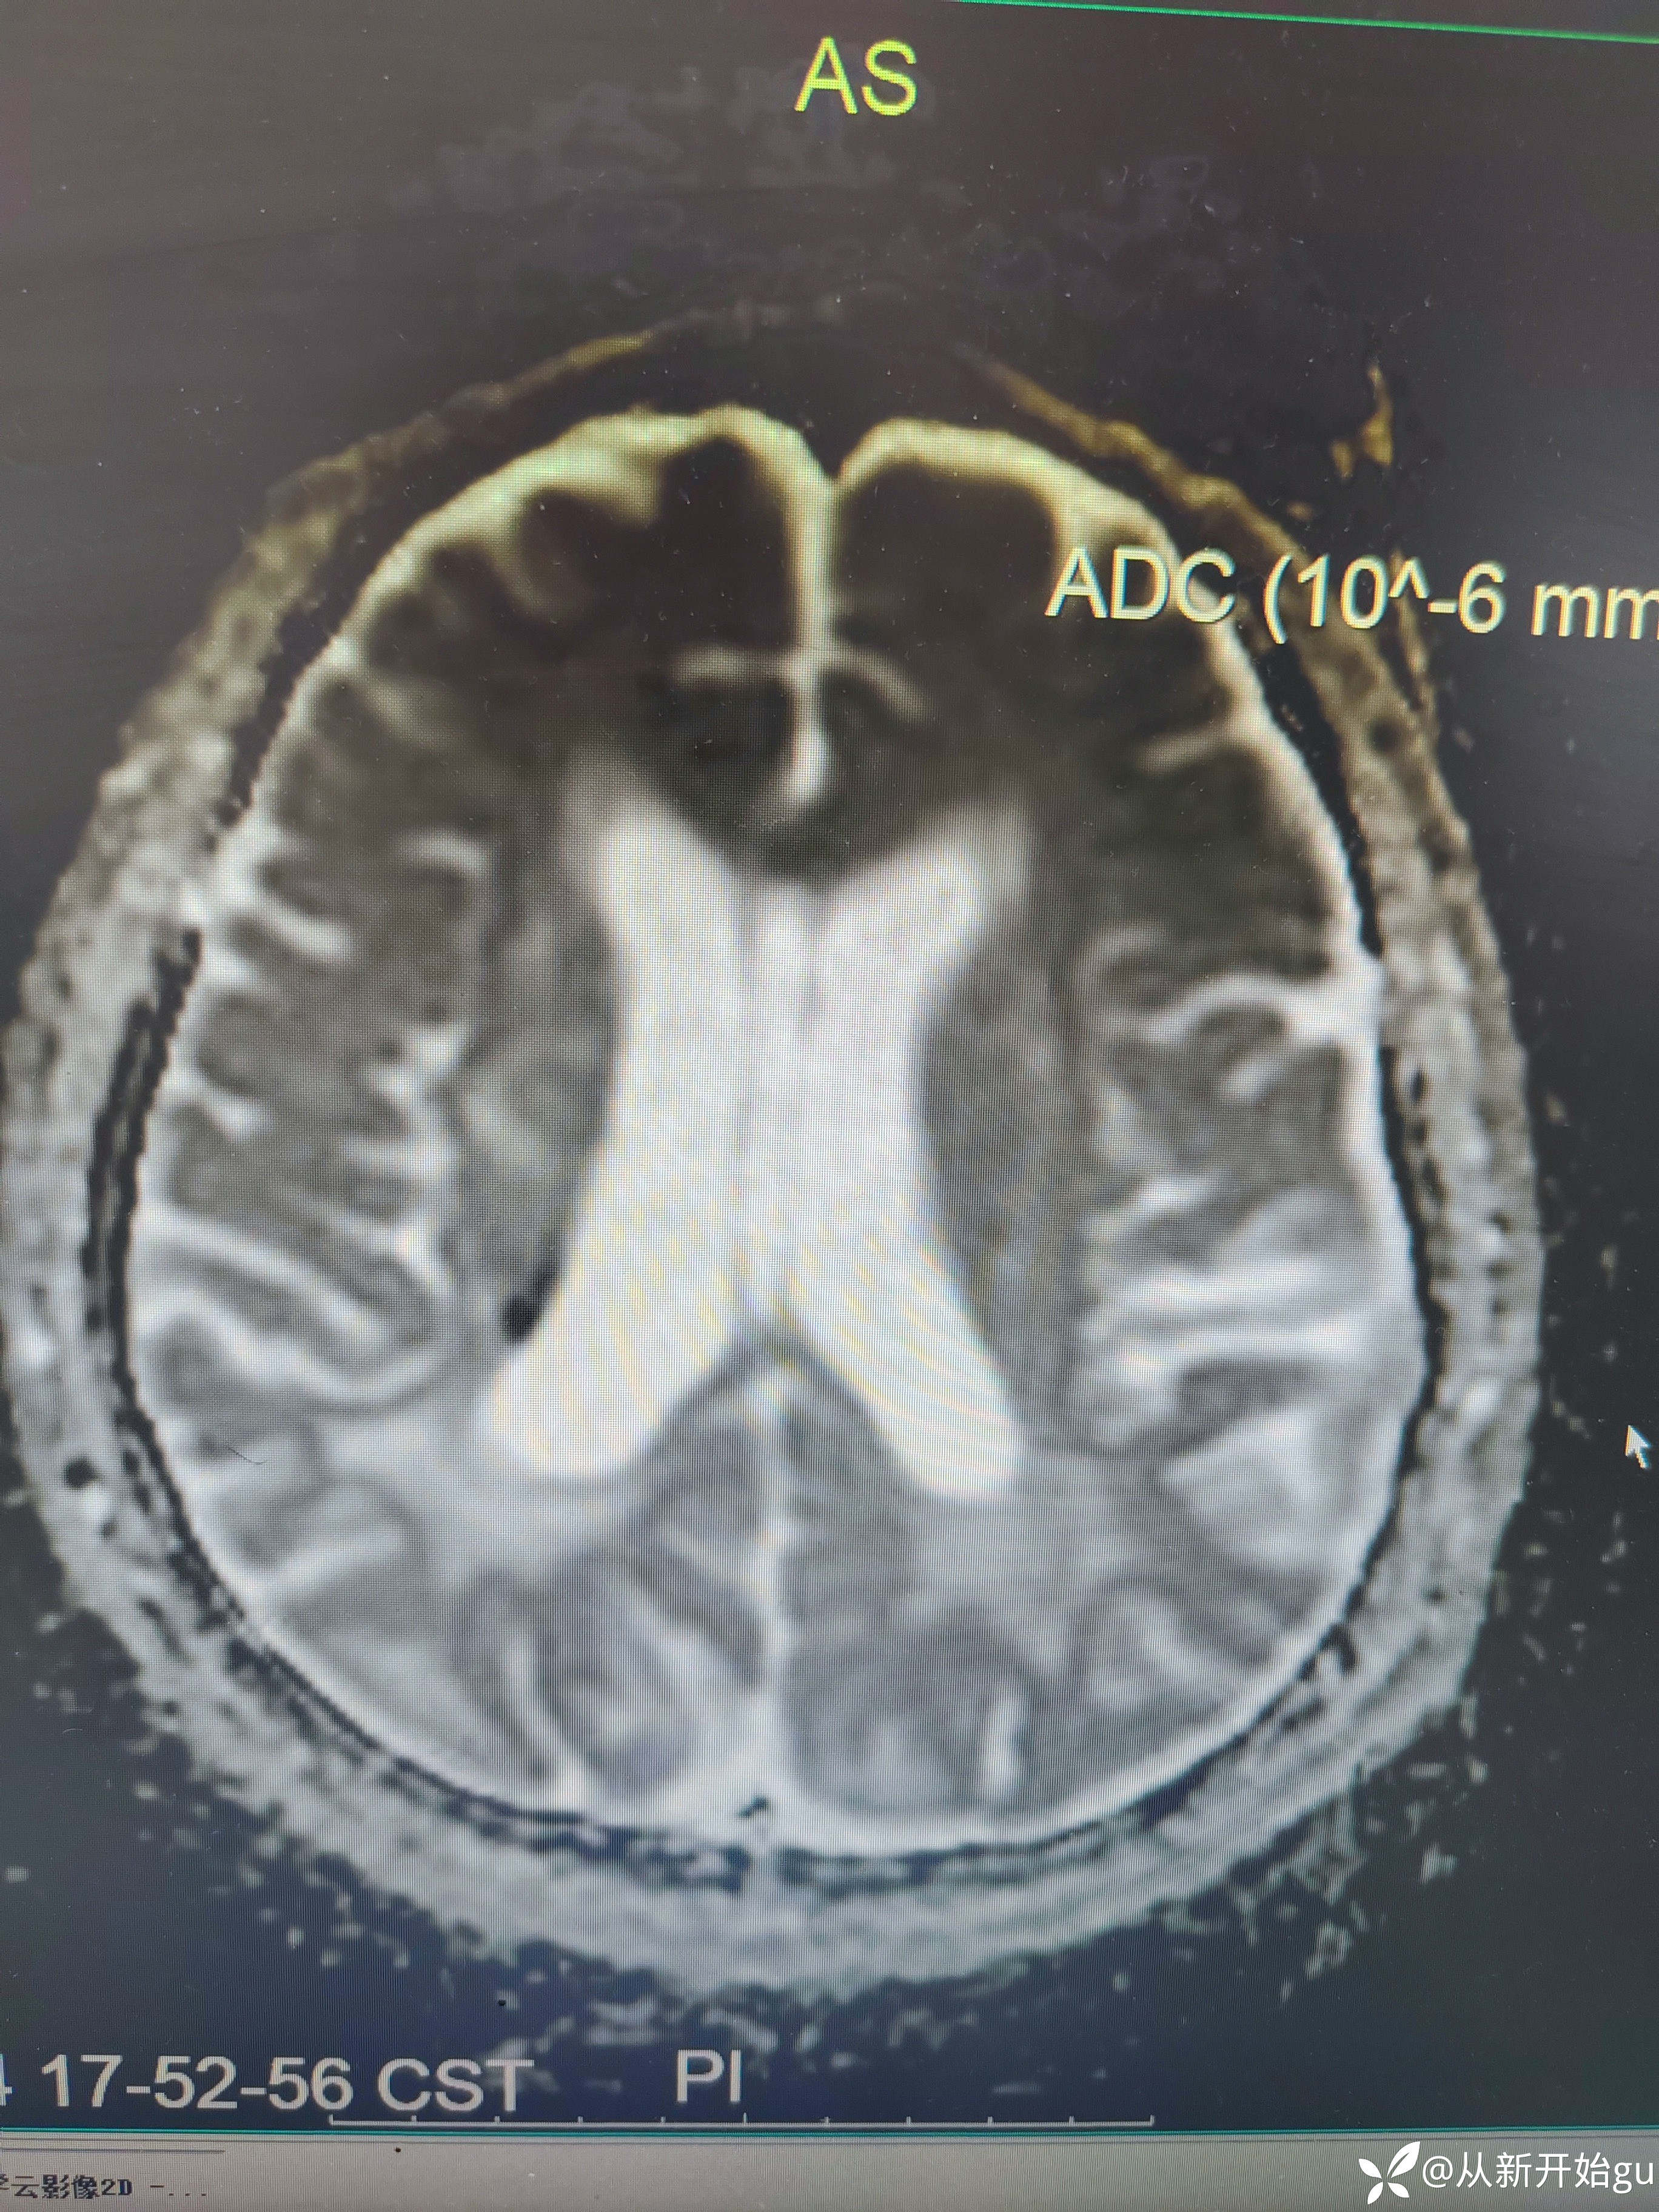

患者男性53岁,主因被发现左下肢活动障碍2.5小时来院,(患者下夜班,于上午9点休息,下午3点醒后出现症状)。既往脑梗死病史9个月,遗留言语不利及口角歪斜的症状。查体:右侧鼻唇沟稍浅,神舌右偏,左侧下肢肌力4级,左侧指鼻试验欠稳准,左侧巴氏征阳性。外院完善颅脑CT无出血改变。来院后完善核磁检查如图所示。